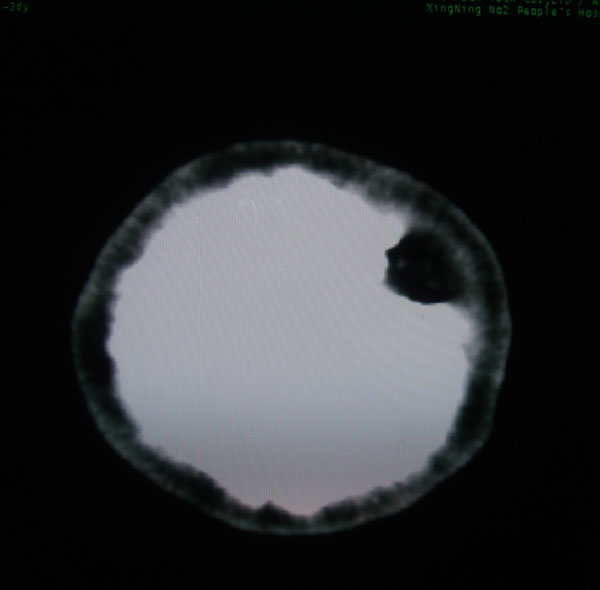

以下是引用拾荒者在2008-6-7 13:05:00的发言:[br]左侧顶骨局限性骨质缺损,边缘锐利,无硬化边,周围软组织轻度肿胀,无明显软组织肿块及骨膜反应,考虑嗜酸性肉芽肿可能。